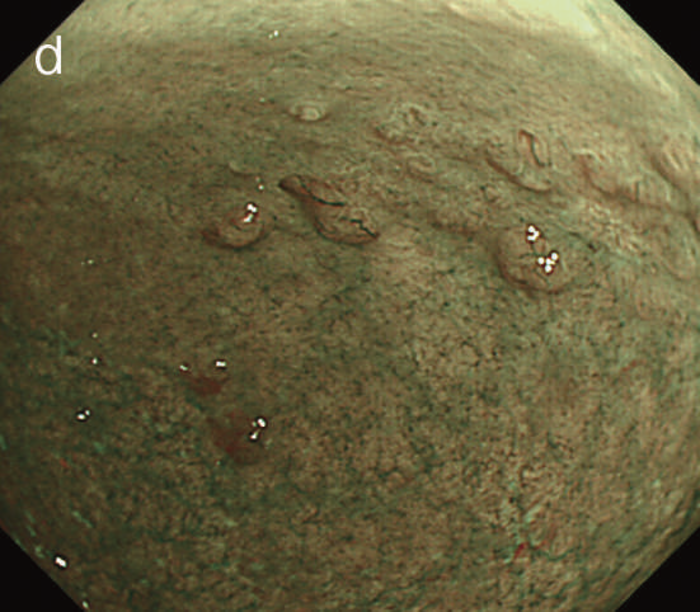

図6 UC関連LGDの内視鏡所見

- 白色光像:直腸(下部直腸)に色調変化は乏しく,微小な隆起を複数認めた。背景粘膜は寛解期にあった。

- NBI非拡大像:Brownishな領域が明らかとなった。

- 色素内視鏡像:病変辺縁が明瞭な微小な隆起を複数伴う表面平坦型病変。

- NBI拡大像:口径整でらせん状の微小血管と絨毛状の表面構造を認めた。

- pit pattern像:小型の類円形,管状pitを認めた。